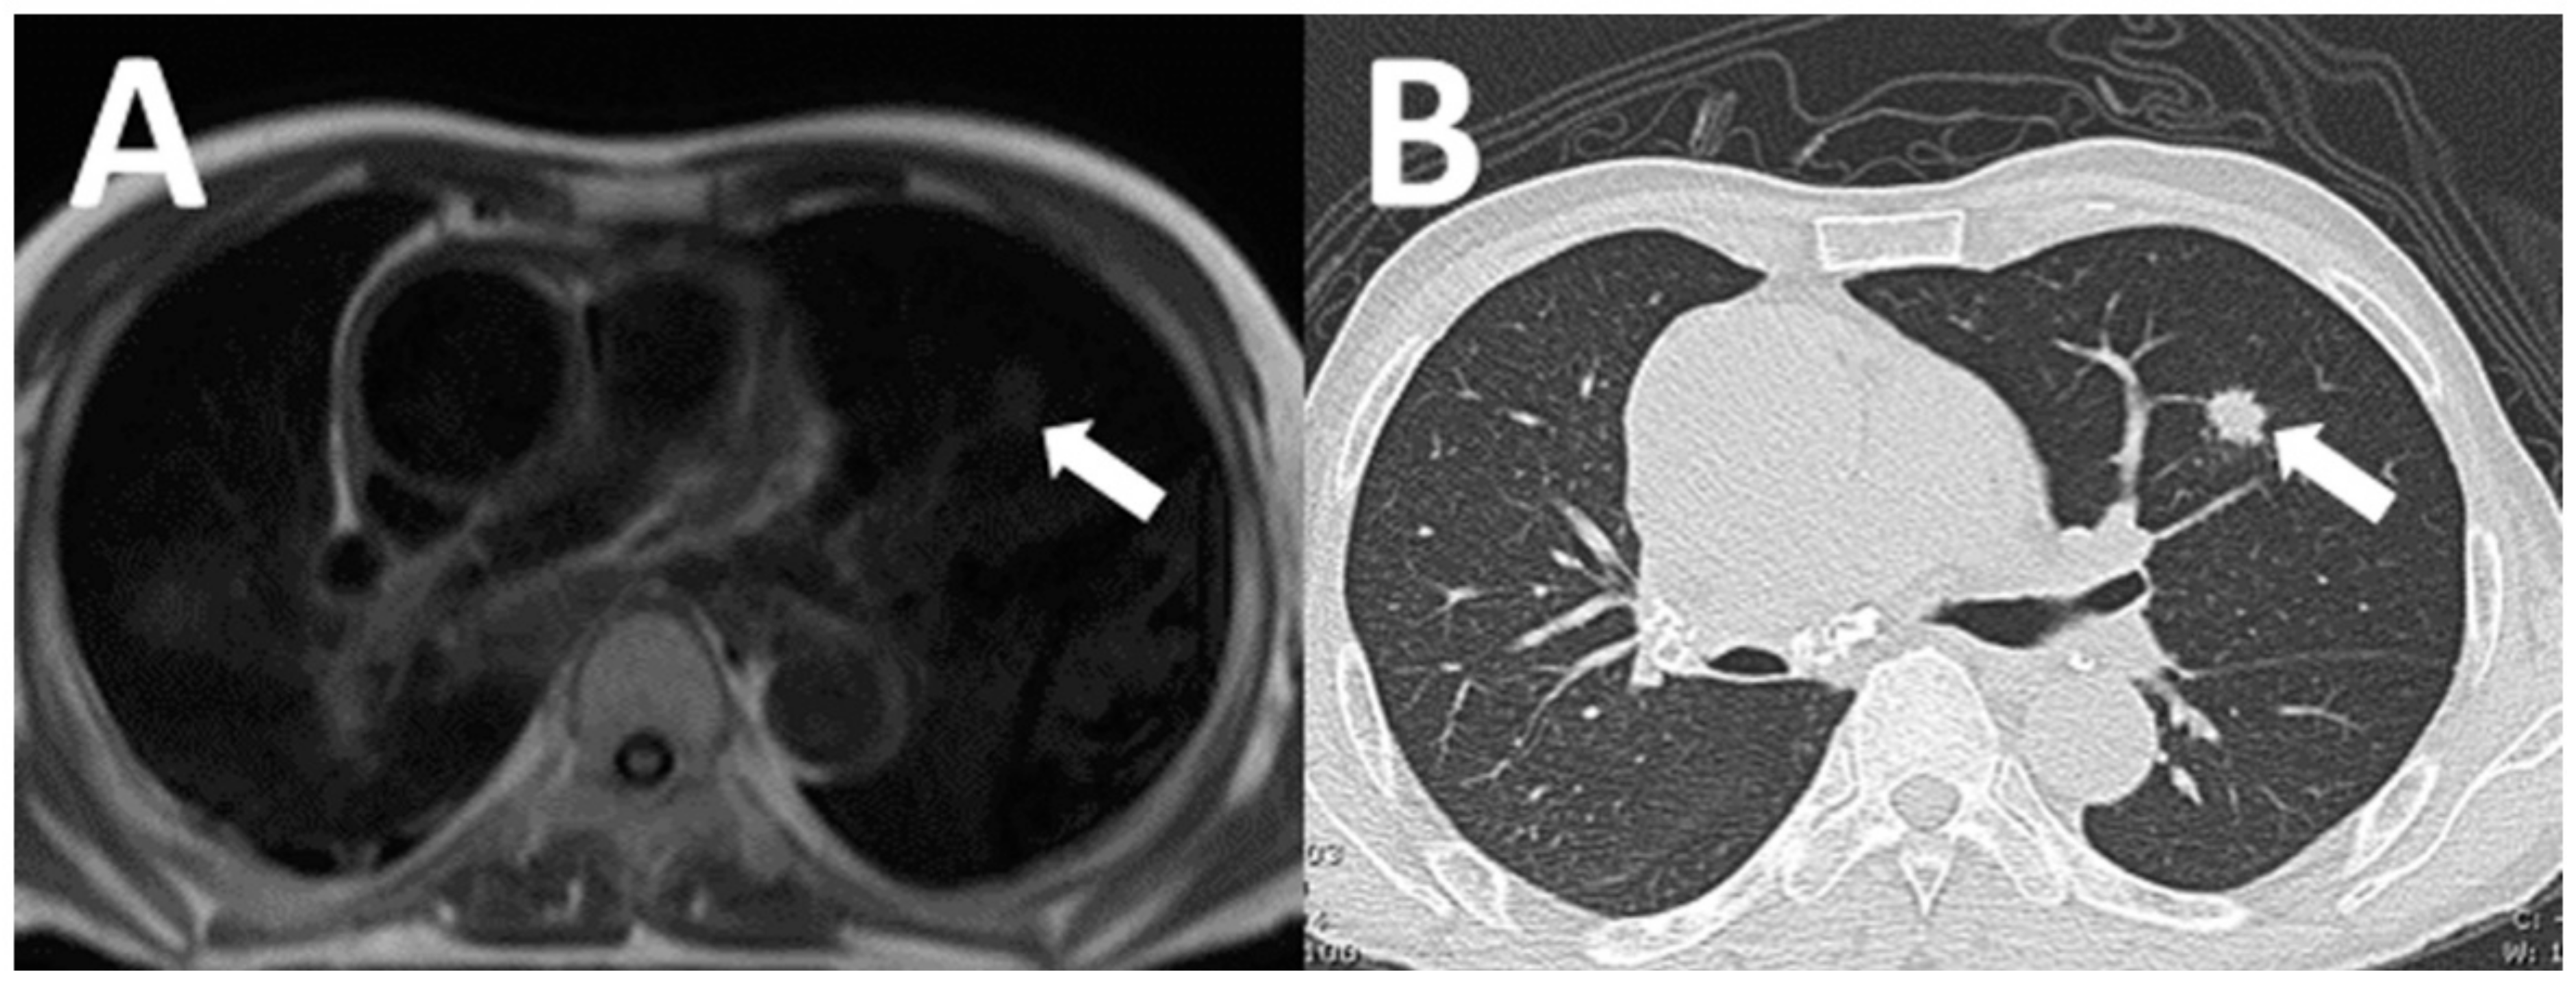

| Clinically significant NCA (n = 25) | |

| Lung cancer | 4 (16) |

| Pulmonary thromboembolism | 2 (8) |

| Aortic dissection | 2 (8) |